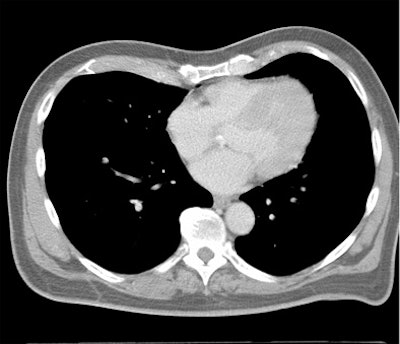

Which image would you rather be responsible for? Small 13-cm FOV (above) provides the best cardiac image quality at the lowest radiation dose compared with medium 25-cm FOV coronary CTA image (below). Thoracic image (bottom) maximizes anatomic coverage but at the cost of additional radiation and potentially more incidental findings. All images courtesy of Dr. Matthew Budoff.

From there, expanding the FOV to the entire thorax for screening of other important findings (lung, breast, axilla, mediastinum, and spine) would actually boost the radiation dose by 67.5%, he said.

Of course, more anatomic coverage is often needed, Budoff said. Sometimes the radiologist needs to look for aortic dissection or pulmonary embolism, but at that point it's not a heart study.